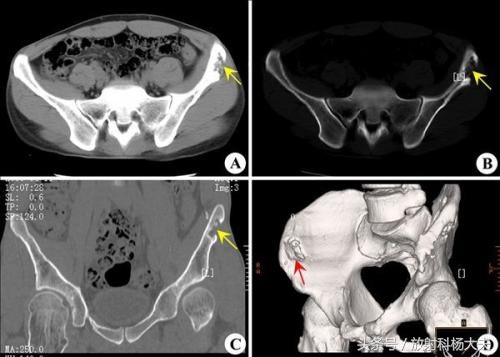

近1年来刘叔左髂腰部肿物增大明显,并伴有行走时间较长后左髂腰部酸胀感,近半年来刘叔出现了腰骶部疼痛的症状。一个月前,刘叔来我院检查,骨科医生要求刘叔做一个骨盆CT检查,骨盆CT检查发现左髂骨翼及左骶髂关节多发骨质破坏并软组织肿胀形成,其内可见不规则高密度灶。影像诊断考虑为左髂骨软骨肉瘤。一周前刘叔做了穿刺活检,活检结果是软骨肉瘤。

来自网络,软骨瘤,良性